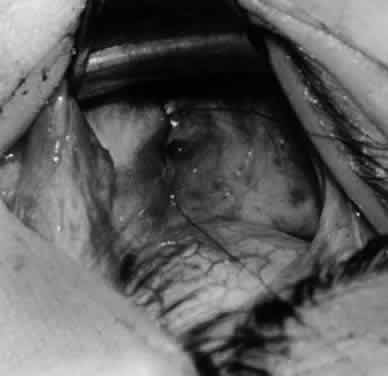

Fig. 5. The Stevens hook is placed adjacent to the posterior edge of the inferior oblique muscle and rotated as the inferior oblique muscle is drawn into the operative field. A forceps is used to retract the redundant Tenon's capsule, encapsulated fat, and intermuscular septum as the muscle is drawn further into the operative field with the Stevens muscle hook.

Fig. 6. The Westcott scissor is used to open the intermuscular septum along the posterior border of the inferior oblique muscle. Care is taken to cut adjacent to the tip of the Stevens muscle hook. This incision is important because it helps to avoid damaging the Tenon's capsule and releasing fat, which leads to the adherence syndrome and postoperative hypotropia.